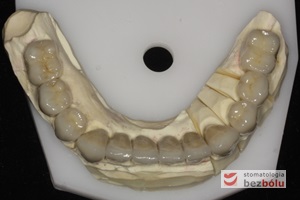

Model gipsowy żuchwy z szablonem chirurgicznym - metalowe tuleje wyznaczają miejsce wprowadzenia wszczepów - widoczne w obrazie RTG

Model gipsowy żuchwy z szablonem chirurgicznym – metalowe tuleje wyznaczają miejsce wprowadzenia wszczepów – widoczne w obrazie RTG

Szablon chirurgiczny oparty o zęby żuchwy - miejsca dla implantów siekaczy wyznaczają tuleje

Szablon chirurgiczny oparty o zęby żuchwy – miejsca dla implantów siekaczy wyznaczają tuleje